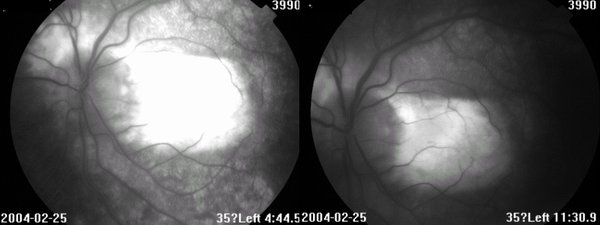

眼底见:玻璃体尘状混浊 眼底图 右眼 左眼 荧光造影图 眼科B超 OCT 视野 讨论: 1、诊断及鉴别诊断

2、眼底见病灶起自视乳头,葡行性发展,呈地图状,界清

3、有CNV,表现为网膜下出血、渗出

4、FFA:早期低荧光,晚期高荧光;有荧光渗漏(CNV)、遮挡荧光(出血)

FFA:早期低荧光,晚期高荧光;如有CNV,可见荧光渗漏,或出血遮挡荧光。晚期病例:病灶边缘高荧光,中央低荧光,经常见大的脉络膜血管